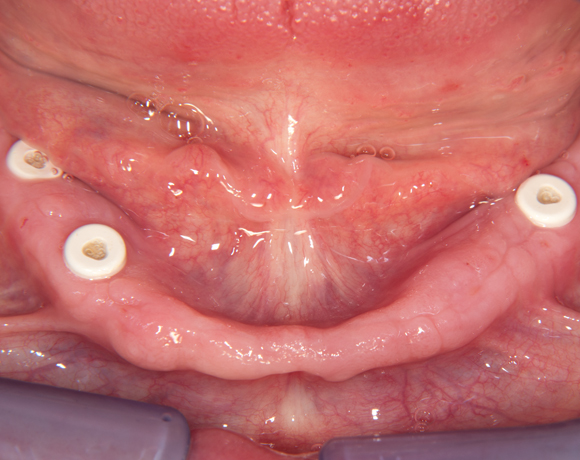

Fixierung einer Unterkiefervollprothese mit vier Implantaten

Mit Implantaten und dem Locatorsystem lassen sich Prothesen gut fixieren und geben einen guten Halt zum Essen und Sprechen

61 jähriger Patient, im Ober- und Unterkiefer mit Vollprothesen versorgt. Der Patient litt darunter, dass seine Unterkieferprothese keinen richtigen Halt hatte. So wurde ihm vorgeschlagen mit vier Implantaten und dem Locatorsystem die Prothese am Unterkiefer zu fixieren und damit einen hohen Komfort beim Essen und Sprechen zu ermöglichen. Der Patient entschied sich für eine metallfreie Versorgung. Es wurden Zeramex® P Implantate von Dentalpoint AG verwendet, für die Matrizen das System der Fa. Valoc das Novalocsystem gewählt. Die Verstärkung der Prothese wurde metallfrei mit einem PEEK – Gerüst gewährleistet.